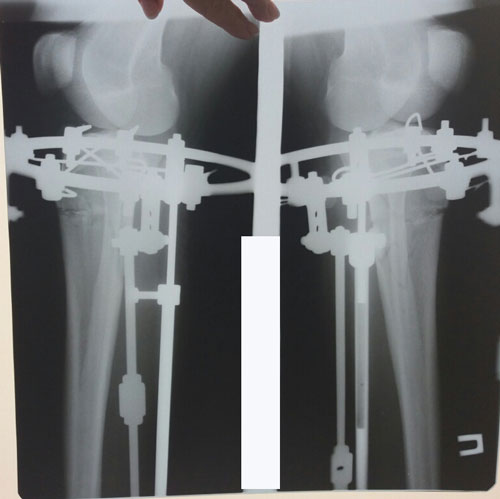

Исходник - 26 лет. Атырау

Дата операции - 16.06.2018г.

Дата снятия аппаратов 29.08.2018г.

Срок сращения 72 дня.